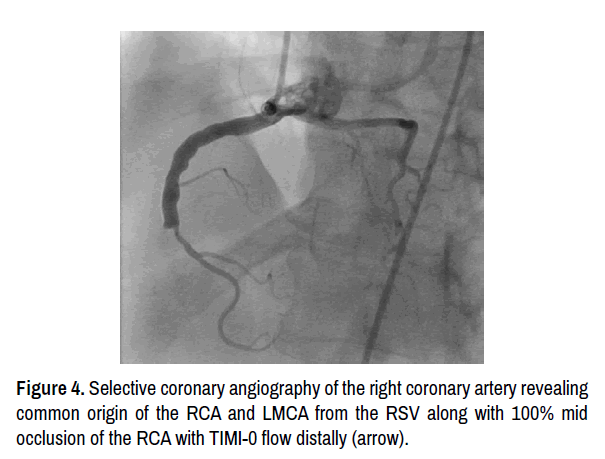

A 67-year-oldCaucasian woman presented to ED with complaints of recurrentand changing pattern of sub-sternal chest pressureradiating to the back and upper jaw. She had history of chronicsmoking. The initial ECG showed old inferior infarct and new T wave abnormality suggestive of ischemia. Coronary angiography was performed due to ongoing symptoms whichrevealed anomalous origin of LMCA from the right coronary cusp. There was 90% stenosis of the mid LCX and 50% stenosis in LAD. RCA had 100% occlusion in mid segment with faint left to right collaterals (Figure 4). CTS was consulted who recommended urgent CABG given high grade stenosis in RCA and LCX. Patientunderwent triple vesselbypass with Left IMA to LAD, Right IMA to OM, and SVG graft to RCA. Patient had an unremarkable post-operative hospital course and was discharged home in a stable condition. One year later, she presented with acute coronary syndrome/NSTEMI. This time, her coronary angiography showed patent SVG-RCA graft with atreticleft and right IMA grafts. The LCX was 90% occluded and underwent successful PCI with drug-eluting stent placement. Medical therapy was continued, and patient continues to be symptom free on subsequent follow-up visits (Figures 4 & 5).

journal-interventional-general-cardiology-origin

Figure 4. Selective coronary angiography of the right coronary artery revealing common origin of the RCA and LMCA from the RSV along with 100% mid occlusion of the RCA with TIMI-0 flow distally (arrow).